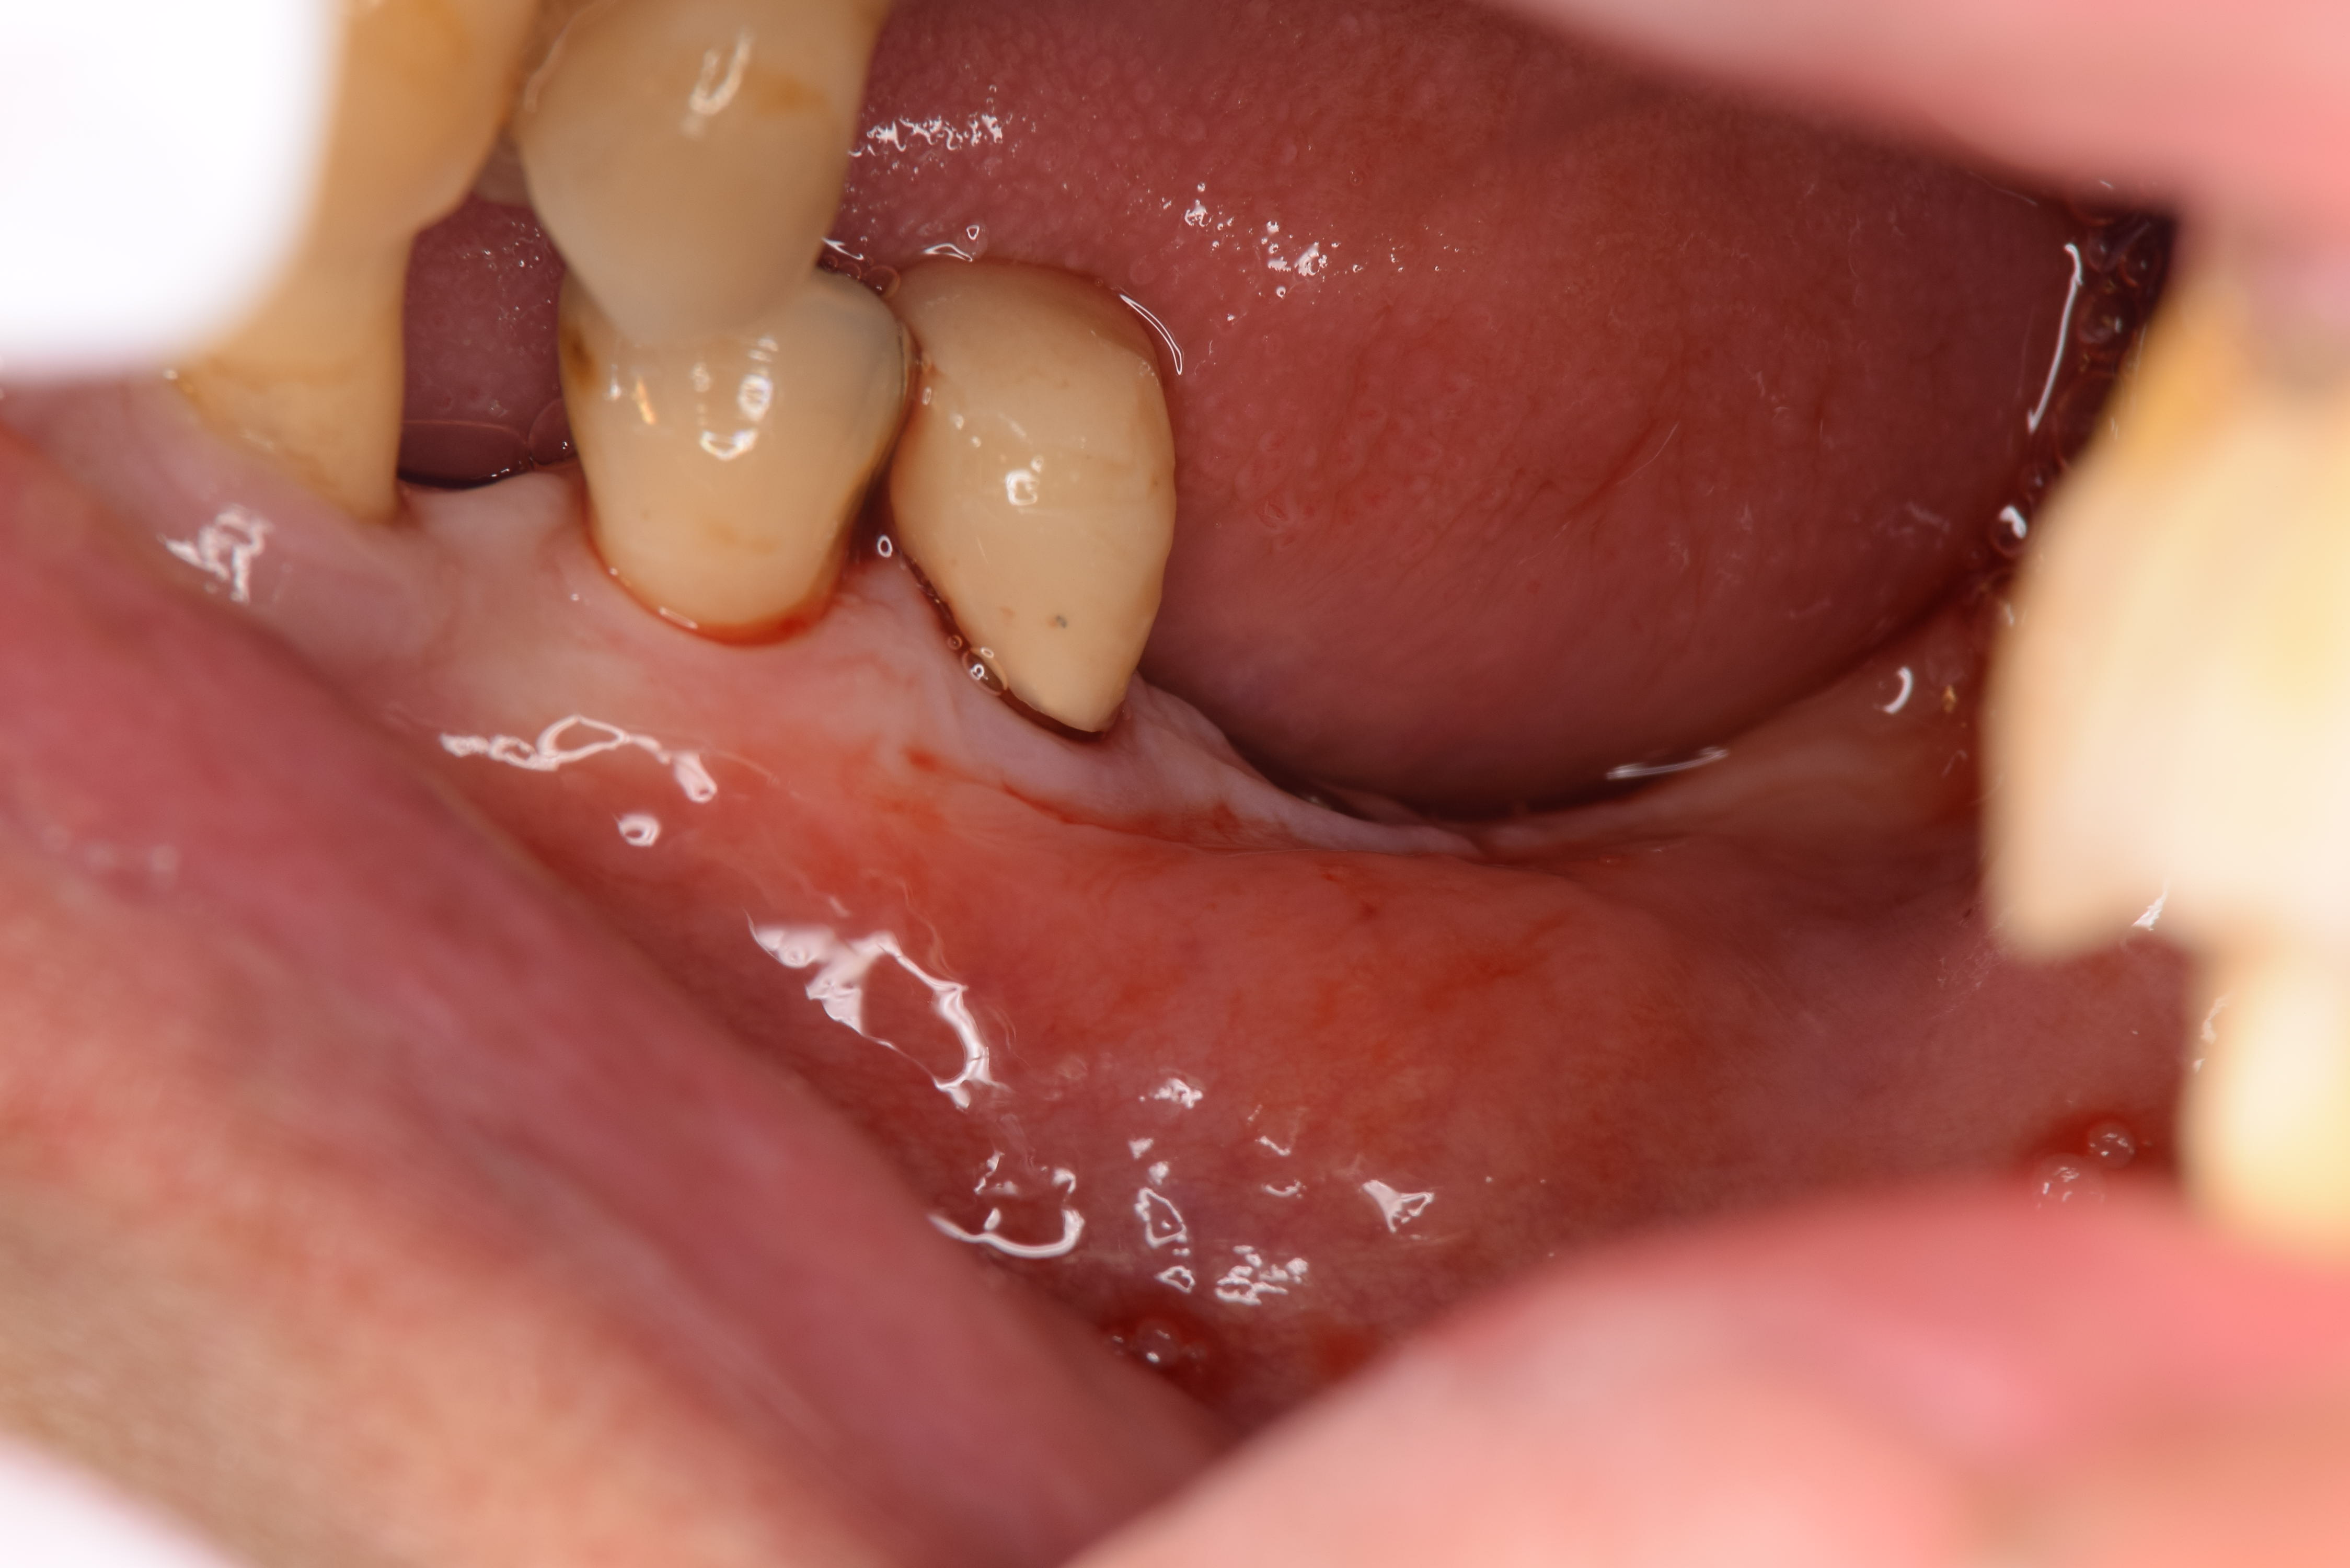

術前の状態です。(ミラー像)これをヨードで染めると角化粘膜と非角化粘膜の状態がわかります。

上顎の口蓋(上の顎の内側)の歯肉が強いためそこから歯肉を採取します。